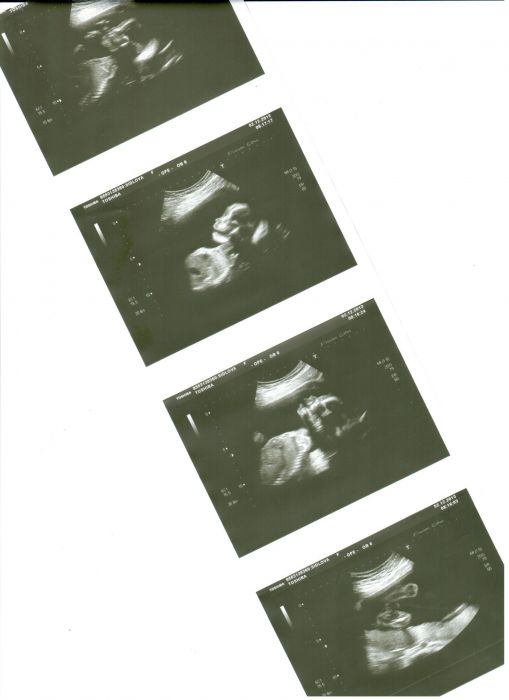

Tady je náš aktualní snímek z 2.12.2013